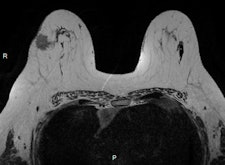

Invasive ductal carcinoma with positive axillary lymphadenopathy. The detection of malignant masses is relatively easy using DWI for both index tumor and axillary positive lymph node. ADC values of the index tumor and positive homolateral lymph node were less than 0.9. This case illustrates the usefulness of DWI to detect both index tumor and positive lymphadenopathy. Images courtesy of Dr. Isabelle Thomassin-Naggara.